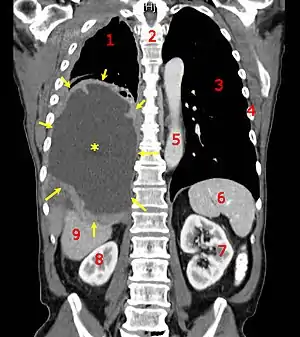

| A coronal CT scan showing a malignant mesothelioma Legend: → tumor ←, ✱ central pleural effusion, 1 & 3 lungs, 2 spine, 4 ribs, 5 aorta, 6 spleen, 7 & 8 kidneys, 9 liver | |